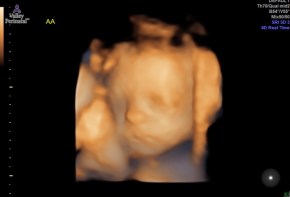

The MFM specialist appointment went much better than the 3-hour test. It was confirmed that the girls are measuring about 2 weeks behind, but their blood flow is good and everything else is measuring well. With their blood flow and how active they are the specialist isn’t concerned about their health, which is a huge relief. He said the ‘by the book’ solution is to up the number of appointments to 2 times a week to better monitor their growth and hearts, but since everything looks great and they are just small he said it’s up to us if we want to up the

number of appointments or if we want to stay on the current appointment schedule. We will discuss our options with the doctor when we see them next Tuesday. We got a lot of really good pictures of Baby A at the ultrasound, and while Baby B let the tech get some pictures she wasn’t as cooperative as A.